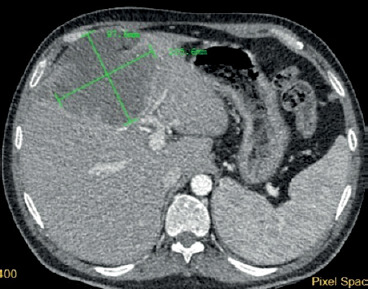

Primary squamous cell carcinoma of the liver.